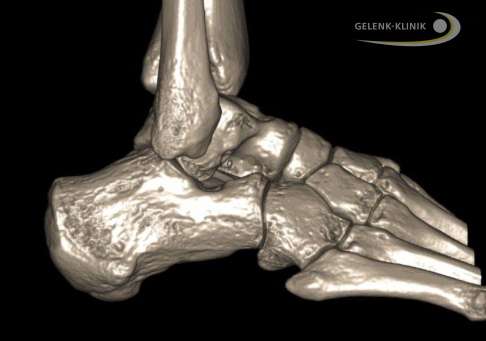

Bildgebende Diagnostik: Röntgen, DVT, MRT

Auf Röntgenbilder finden wir eindeutige Hinweise auf degenerative Veränderungen von Sprunggelenk und Fußgelenken. Unter Belastung – also im Stehen – können wir zudem eine Fehlstellung des Fersenbeines in mehreren Ebenen auf den Bildern zeigen. Des Weiteren untersuchen wir die Vorfußstellung im Verhältnis zum Rückfuß.

Das MRT-Bild (Magnetresonanztomografie) zeigt uns den Status von Sehnen, Bändern und Weichteilgeweben.

Mithilfe des DVT (digitale Volumentomografie) können wir einen Einblick in die genauen räumlichen Darstellungen der knöchernen Verhältnisse der beteiligten Fußknochen bekommen.